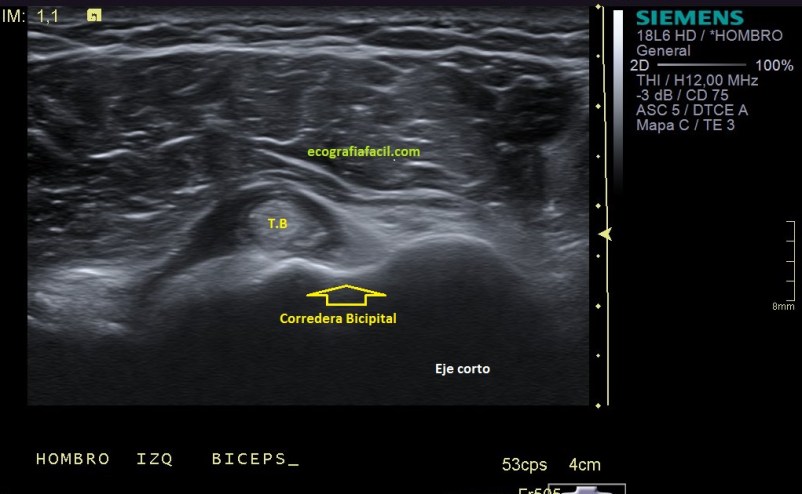

Vamos a partir de la normalidad y te vienes a ver ahora la patología que hoy nos ocupa, mira. En ocasiones podemos encontrarnos la imagen patológica que indica luxación del tendón, imagen 2. Es un corte en Eje corto. Ves la corredera bicipital vacía, el tendón fuera de su localización habitual, hacia medial, como es habitual, pero conservando la ecoestructura.

Efectivamente, verás que bordeando el tendón existe una mínima cantidad de líquido que está envolviendo u ocupando la vaina del tendón, se ve anecoico y efectivamente es cierto, si lo has visto, enhorabuena, a parte de la luxación, esa es la otra semiología evidente que podemos ver en la imagen 2.